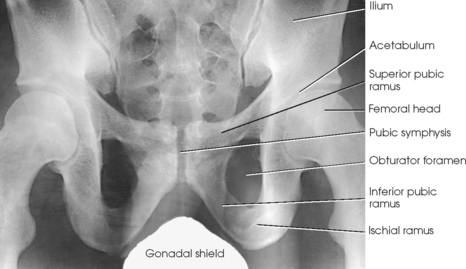

Protection of the patient from unnecessary radiation is a professional responsibility of the radiographer (see Chapter 1 for specific guidelines). In this chapter, the Shield gonads statement at the end of the Position of part section indicates that the patient is to be protected from unnecessary radiation by restricting the radiation beam using proper collimation. In addition, placing lead shielding between the gonads and the radiation source is appropriate when the clinical objectives of the examination are not compromised (Figs. 7-13 and 7-14).

Structures shown: The image shows an AP projection of the pelvis and of the head, neck, trochanters, and proximal one third or one fourth of the shaft of the femora (Fig. 7-18).

The ischium consists of a body and the ischial ramus. The body of the ischium forms approximately two fifths of the acetabulum posteriorly (see Figs. 7-2 and 7-3). It projects posteriorly and inferiorly from the acetabulum to form an expanded portion called the ischial tuberosity. When the body is in a seated-upright position, its weight rests on the two ischial tuberosities. The ischial ramus projects anteriorly and medially from the tuberosity to its junction with the inferior ramus of the pubis. By this posterior union the rami of the pubis and ischium enclose the obturator foramen. At the superoposterior border of the body is a prominent projection called the ischial spine. An indentation, the lesser sciatic notch, is just below the ischial spine.

The pubis consists of a body, the superior ramus, and the inferior ramus. The body of the pubis forms approximately one fifth of the acetabulum anteriorly (see Fig. 7-2). The superior ramus projects inferiorly and medially from the acetabulum to the midline of the body. There the bone curves inferiorly and then posteriorly and laterally to join the ischium. The lower prong is termed the inferior ramus.